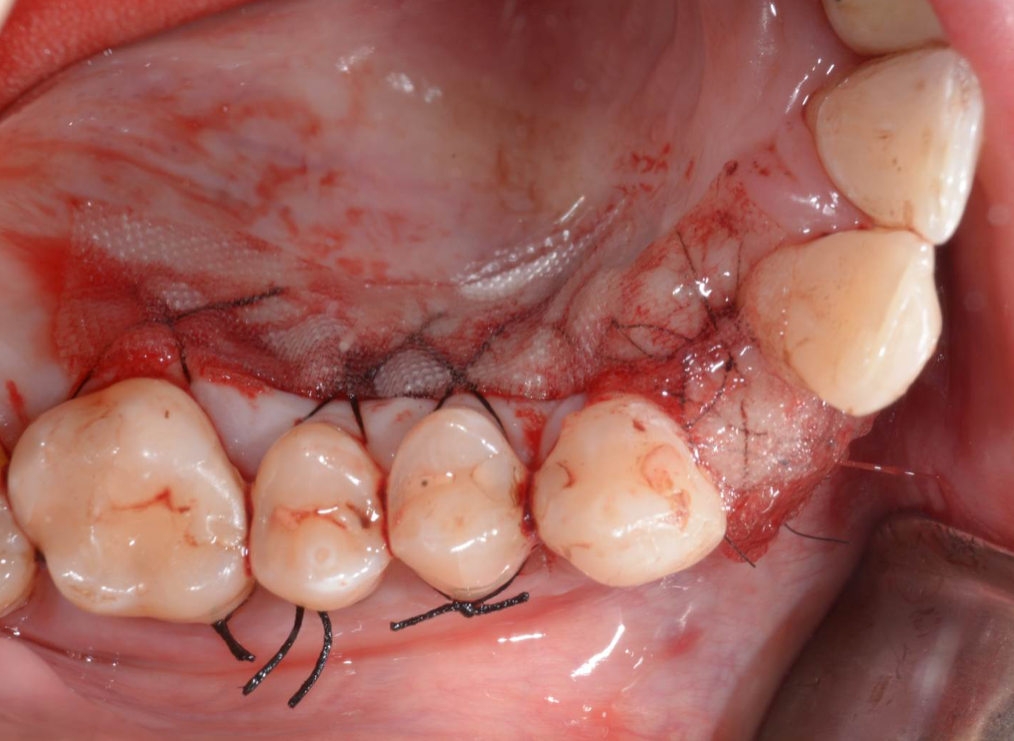

Während oder nach oralen Operationen, von der Extraktion von Zähnen bis hin zu rekonstruktiven Eingriffen, oder Implantationen, bietet BloodSTOP® iX eine schnelle und vorübergehende Kontrolle von Oberflächenblutungen.

BloodSTOP® iX absorbiert schnell Blut und verwandelt sich in ein klares Gel, um die Wunde mit einer transparenten Schutzschicht zu versiegeln, Blutplättchen zu binden und zu aktivieren, sowie die Gerinnung und Wundheilung zu unterstützen.

Anwendungsbeispiele

- Parodontale und chirurgische Wunden